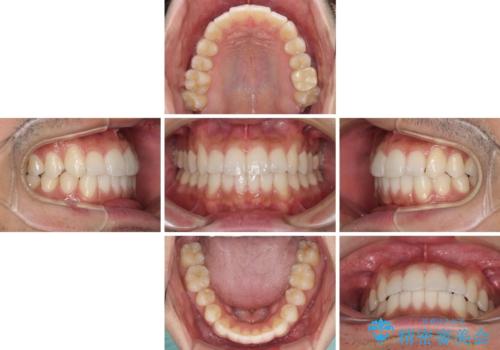

前歯のデコボコを治したい インビザライン矯正治療

- 前歯のデコボコを治したいとのことで来院された患者様です。

上下顎ともに歯列全体の後方移動とIPR(歯と歯の間を削る)によってデコボコが解消するように設計し、インビザラインにより治療を行うこととしました。

毎日22時間以上しっかりとマウスピースを装着していただいたので、スムーズに治療が進みました。歯と歯の間を削ることでうまくスペースコントロールでき、1年強で終えることができました。